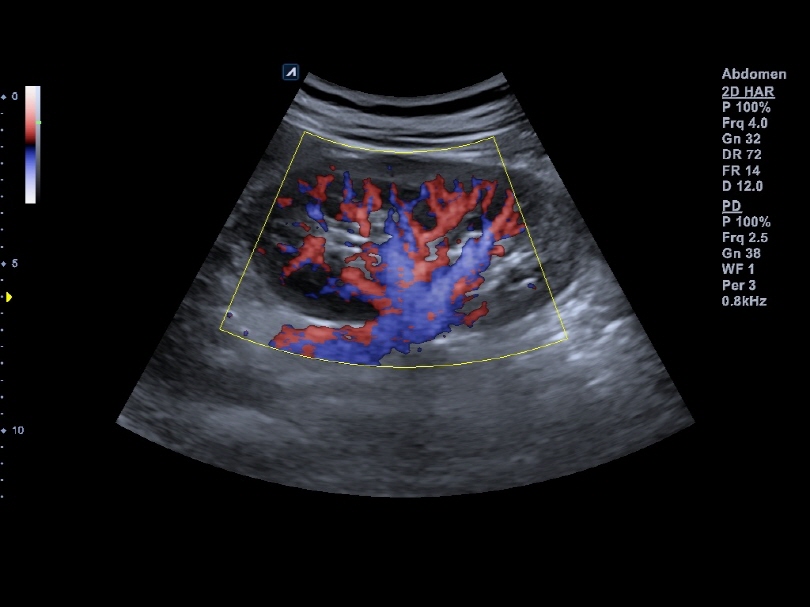

C5-8NT

Microconvex (5-8MHz)

Application:

Abdomen, EM, Cardiac, Pediatric